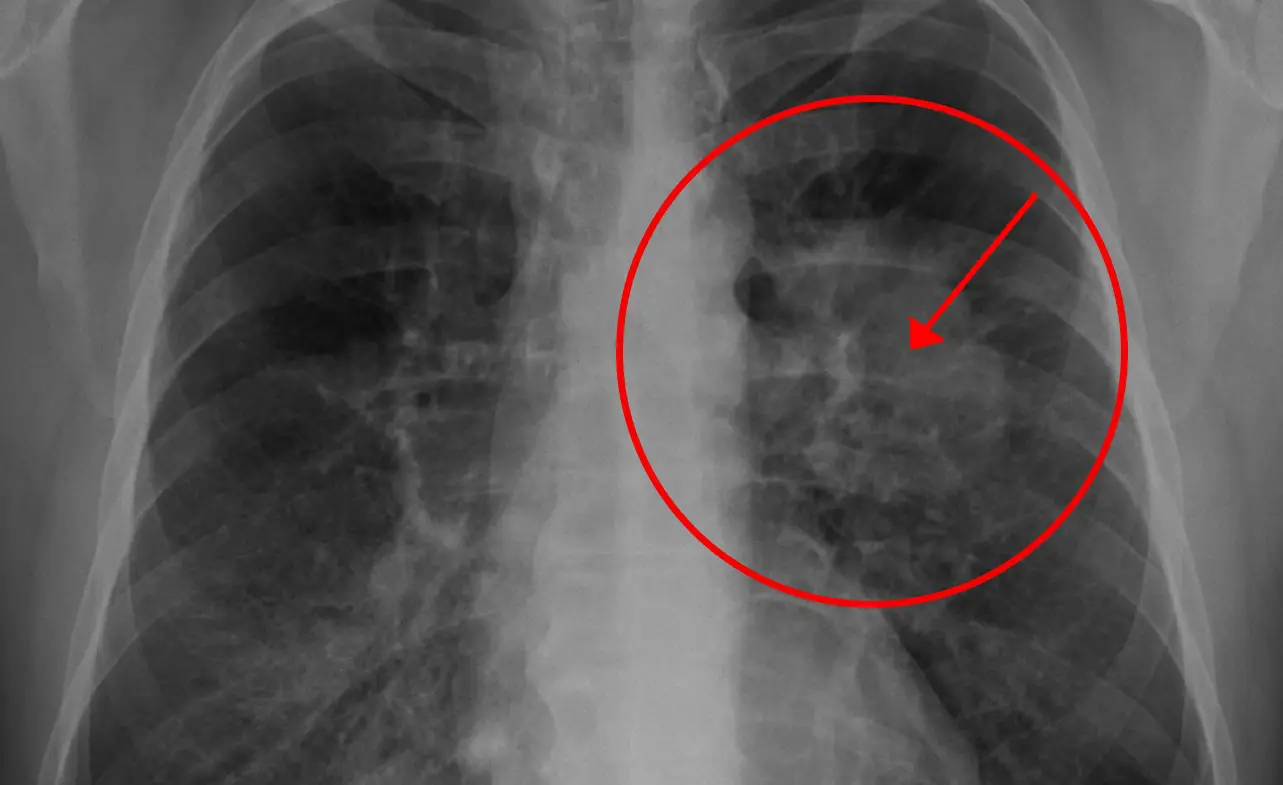

Lung cancer is a type of cancer that forms in the tissues of the lung. There are two main types of lung cancer: non-small cell lung cancer and small cell lung cancer. Non-small cell lung cancer is the most common type, accounting for around 85% of cases. Small cell lung cancer, on the other hand, is more aggressive and less common.

Lung cancer can also be further categorized by stages based on how far it has advanced. The earlier the stage, the easier it is to treat.